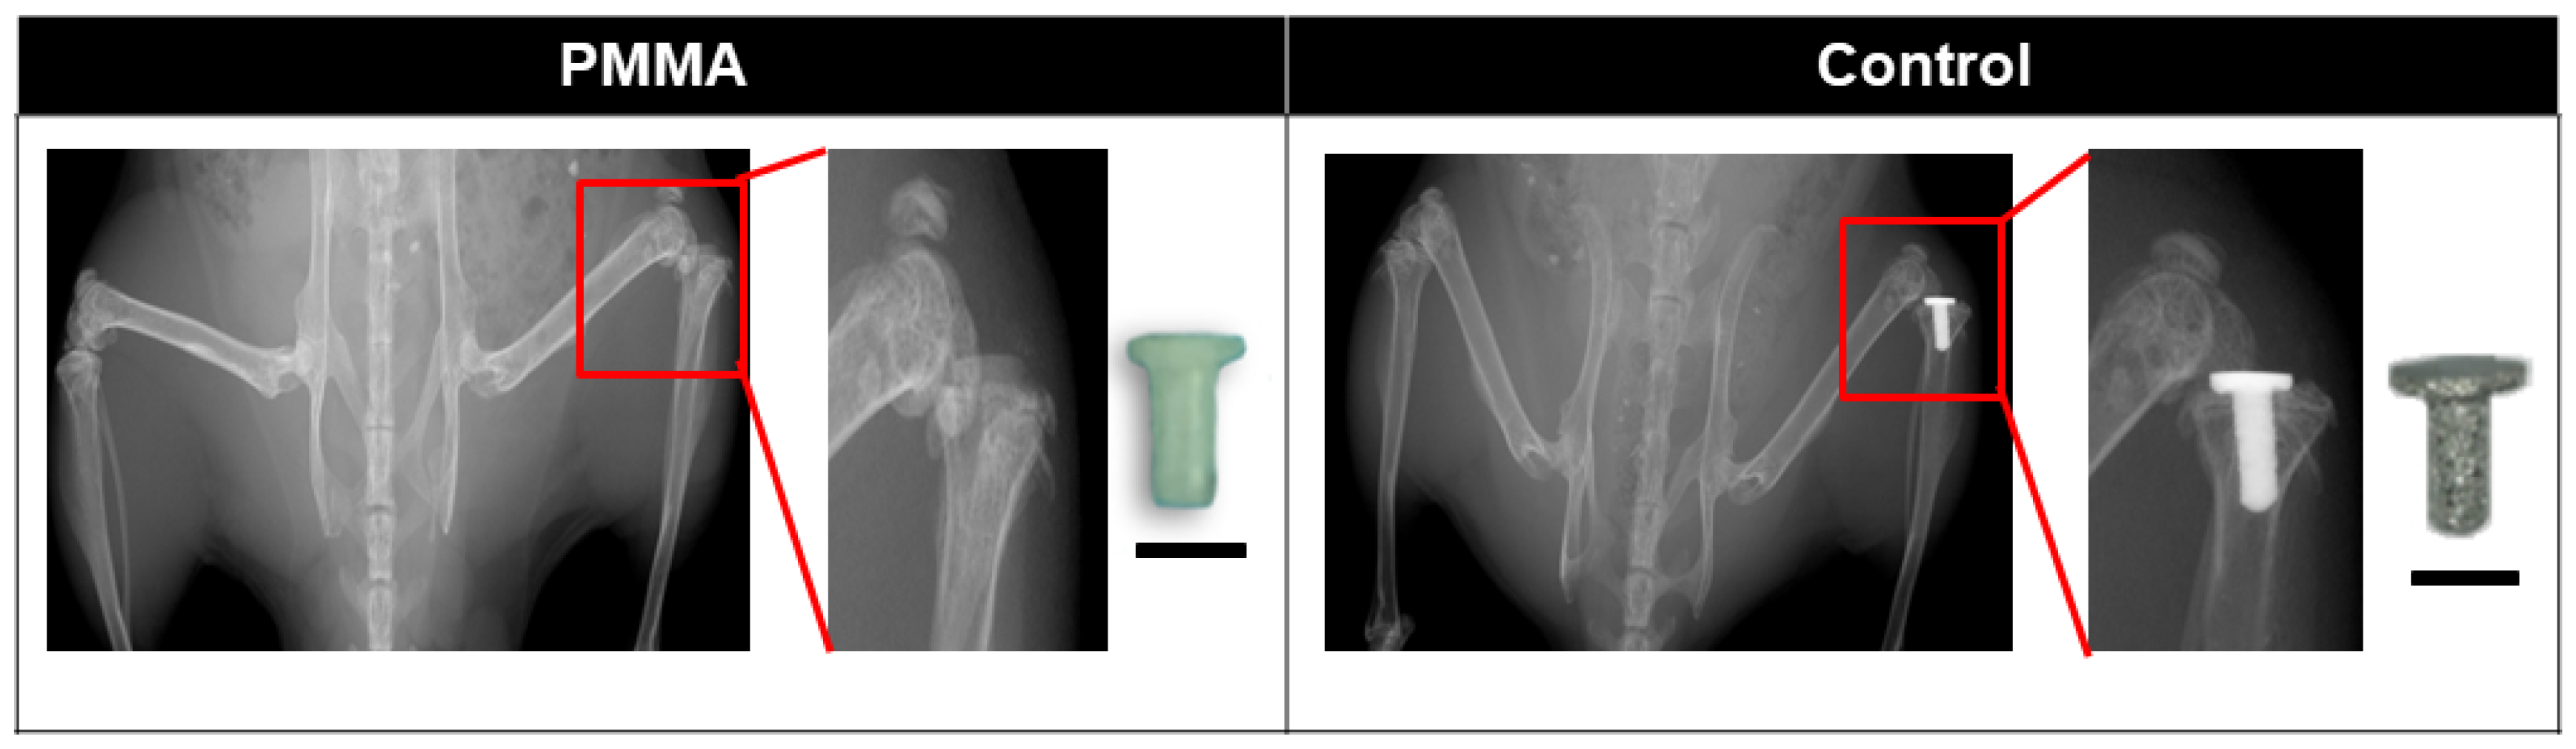

2.2. Osseointegration Model

2.3. Osseointegration Failure Model